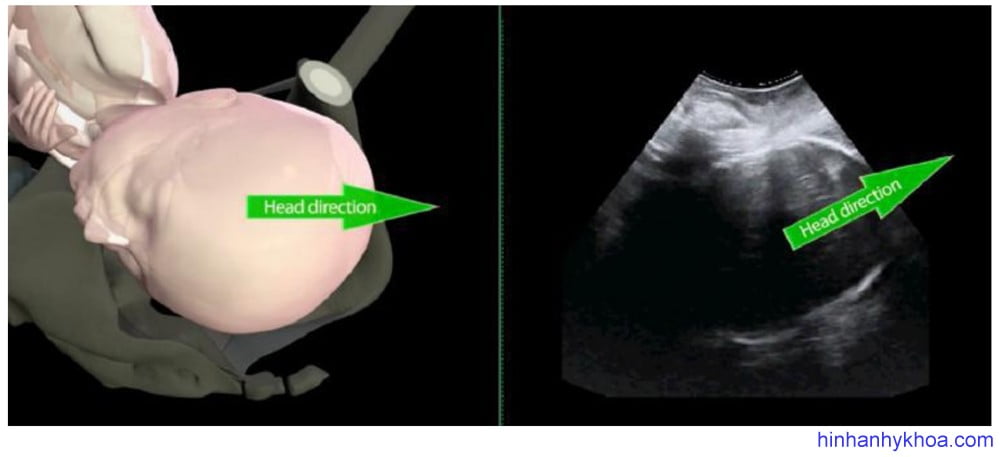

Hướng đầu thai. Là dấu hiệu gián tiếp đánh giá độ lọt thai, được mô tả lần đầu tiên bởi Hendrich và cộng sự42, xác định bởi góc giữa trục dài nhất của phần đầu thai thấy được với trục dọc của xương mu ở mặt phẳng dọc giữa khi siêu âm qua ngã đáy chậu (Hình 5). Xếp loại: đầu đi xuống (góc < 00), đầu đi ngang (góc 0-300) và đầu đi lên (góc > 300). Các tác giả ghi nhận dễ dàng sự thay đổi của hướng đầu thai từ khi đi xuống hướng vào khung chậu, sau

đó đi ngang rồi hướng lên. Khi đầu thai đi hướng lên ngay trước khi thực hiện sinh thủ thuật sẽ cho kết quả thành công dễ dàng hơn.

Hình 5: Hướng đầu thai: ngang (trái) và đi lên (phải).